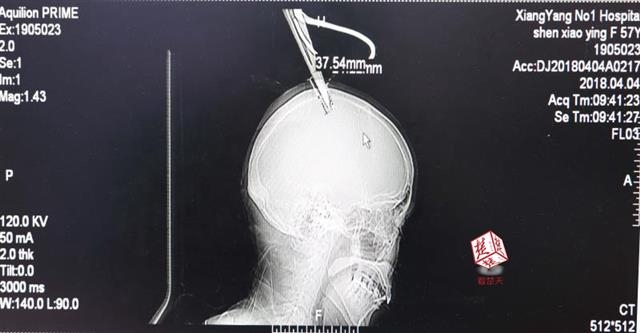

4月4日清晨,襄陽市樊城區(qū)太平店鎮(zhèn)57歲的農(nóng)村婦女沈某,在采摘香椿嫩芽時,綁在竹桿上的剪刀因竹子腐朽不慎折斷,剪刀斜插入頭顱。經(jīng)過及時搶救,目前脫離生命危險。

醫(yī)生檢查發(fā)現(xiàn),剪刀刀尖斜嵌在沈某顱骨里,離腦髓只有兩三毫米。所幸是斜著插進去,如果是垂直刺入,很有可能造成癱瘓。最終經(jīng)過手術,剪刀被取出,沈某目前仍在ICU進一步觀察。